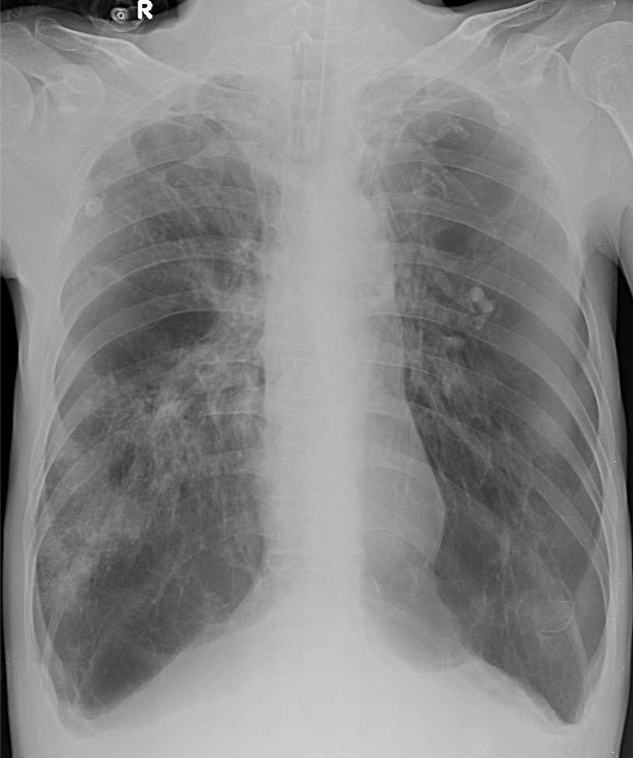

1-Xơ + khí phế thũng rải rác hai phổi 2-Viêm thùy giữa và thùy dưới phổi (P) 3-Tràn dịch + Dày dính màng phổi hai bên 4-Bóng tim nhỏ